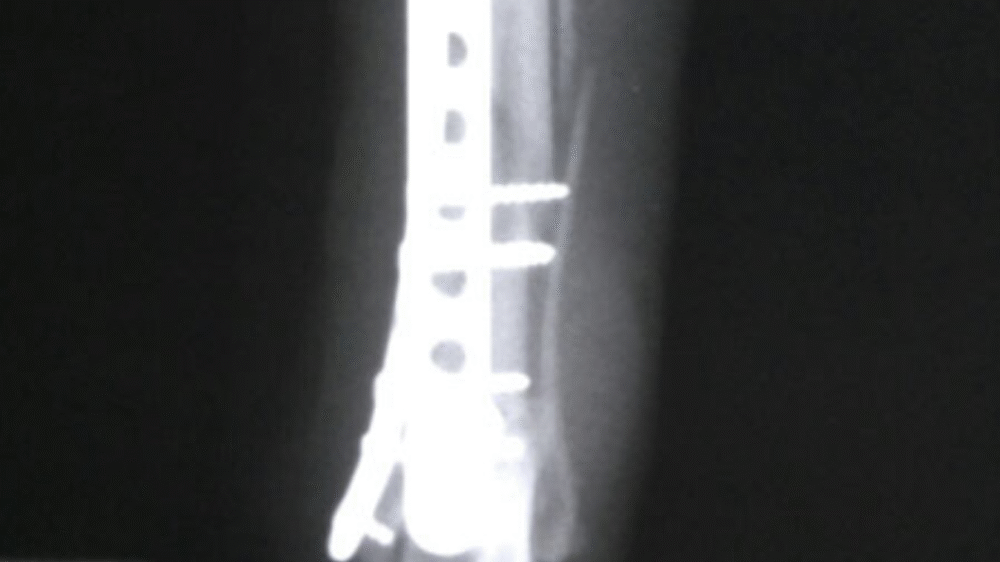

Metatarsal Plating

Example of metatarsal plating.